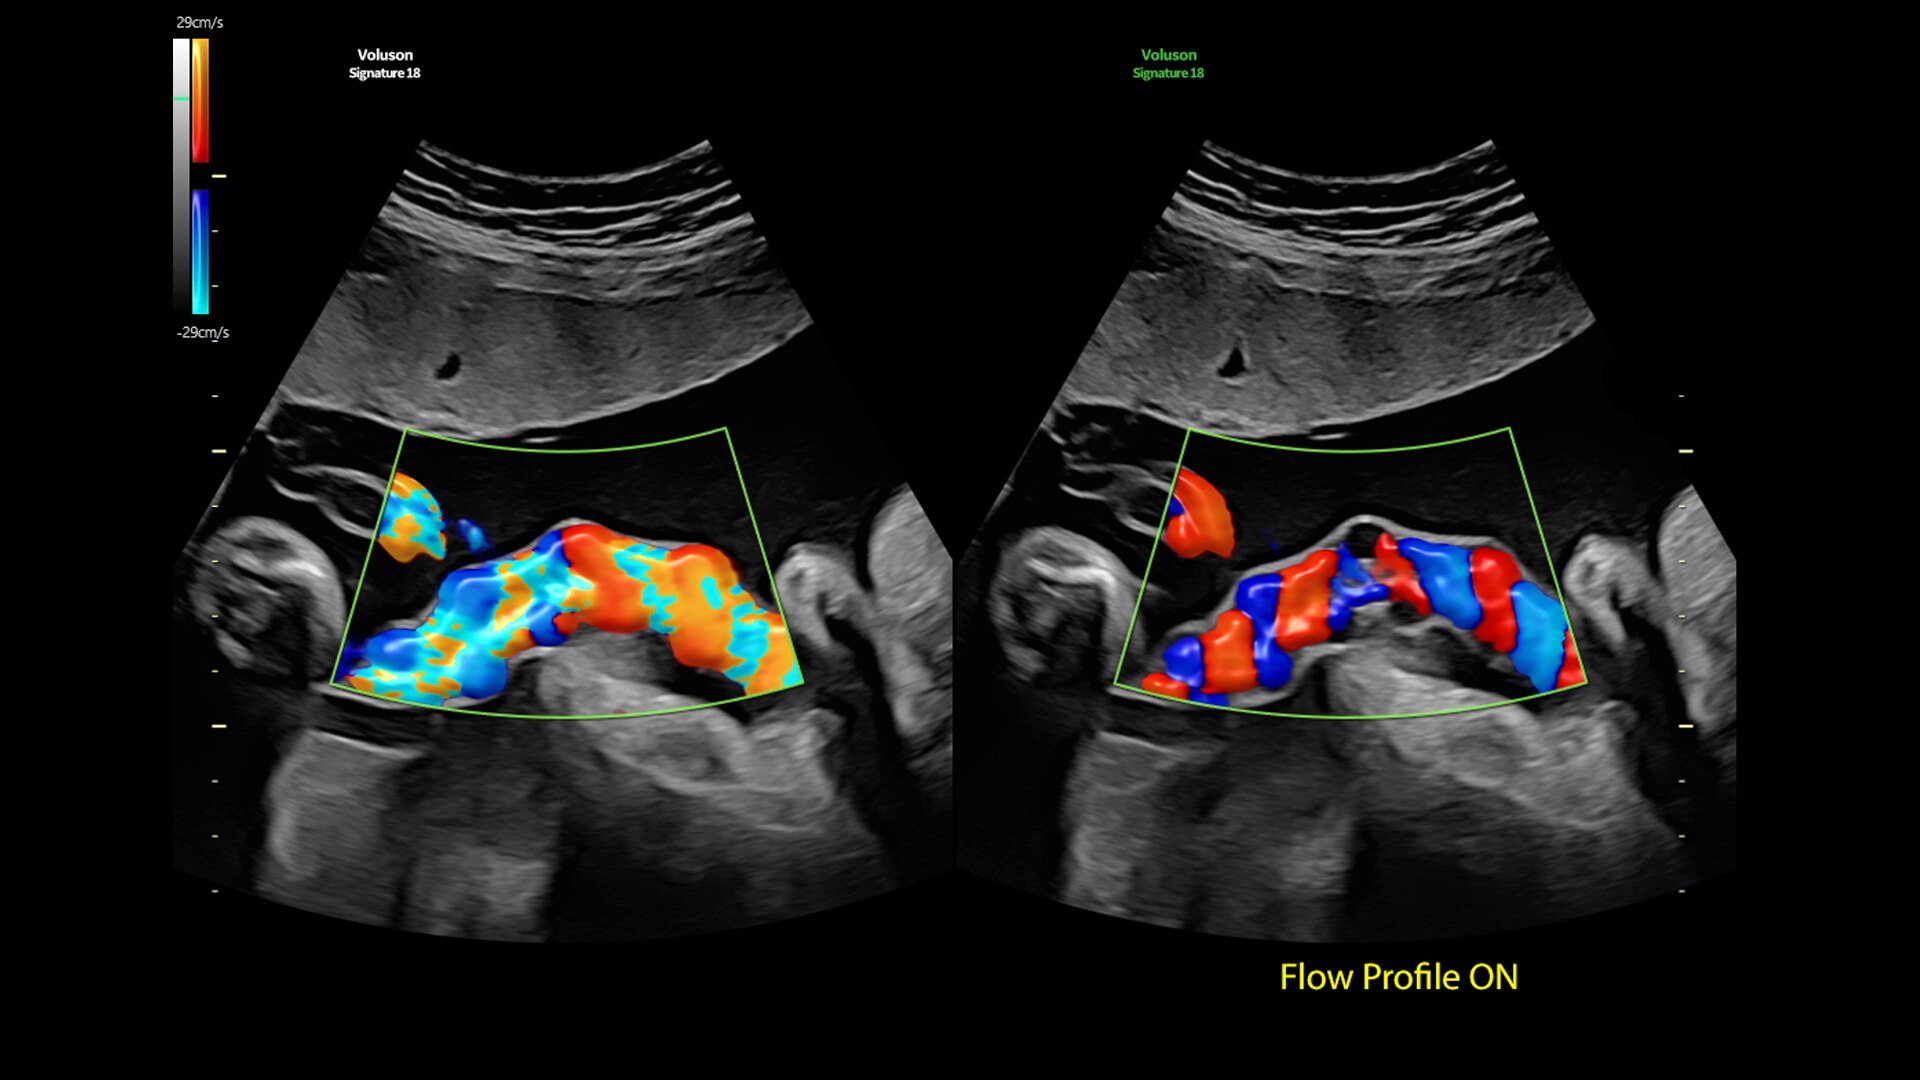

Radiantflow

Fast, easy 3D-like blood flow visualization

Next level color Doppler delivers exceptional sensitivity for easy, fast visualization of blood flow, revealing even the tiniest vessels.

Flow Profiles

Reduce exam time by 56% with Flow Profiles. Dramatically simplifies color and pulsed-wave Doppler optimization by utilizing predefined and optimized settings.